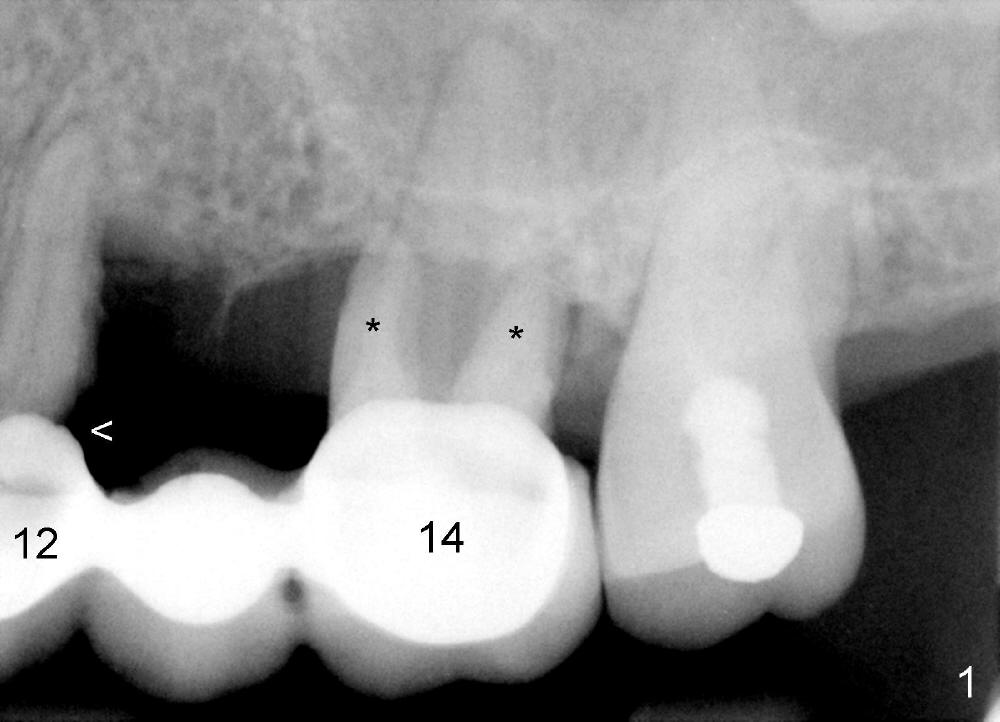

A 53-year-old lady has a failing bridge (Fig.1). There is severe bone loss around the buccal roots of #14 (*). Purulent discharge is from the gingival sulcus (Fig.2 <) with localized gingival erythema and edema (*). When the bridge is removed, the tooth #12 is found nonsalvageable (Fig.3,4). These two teeth are to be replaced by immediate implants (Fig.5). Although the sinus floor is low buccally (arrowheads), a 6x14 mm gingiva-level implant can be placed in the septum close to the palatal socket or in the palatal socket at the site of #14.